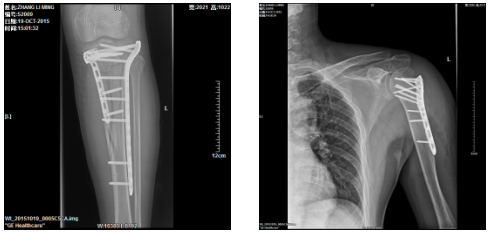

1、开展了从颈椎、胸椎、腰骶椎的椎弓根钉内固定和微创手术。

3、复杂性关节内骨折的内固定手术。

6、四肢骨折的复位内固定术。